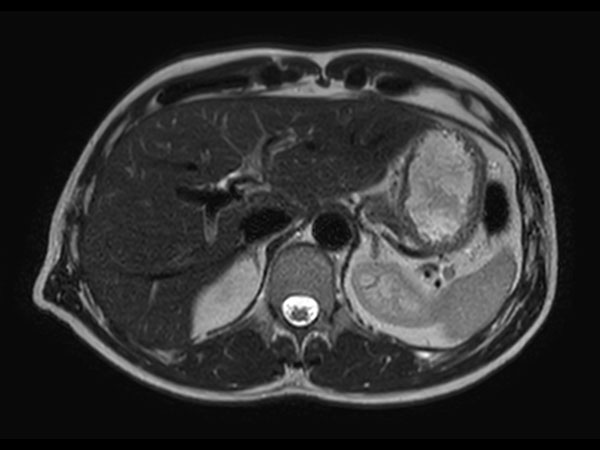

Helium-free MR operations:

Liver on BlueSeal magnet

Spital Uster, Switzerland

• Coil

• Clinical Application